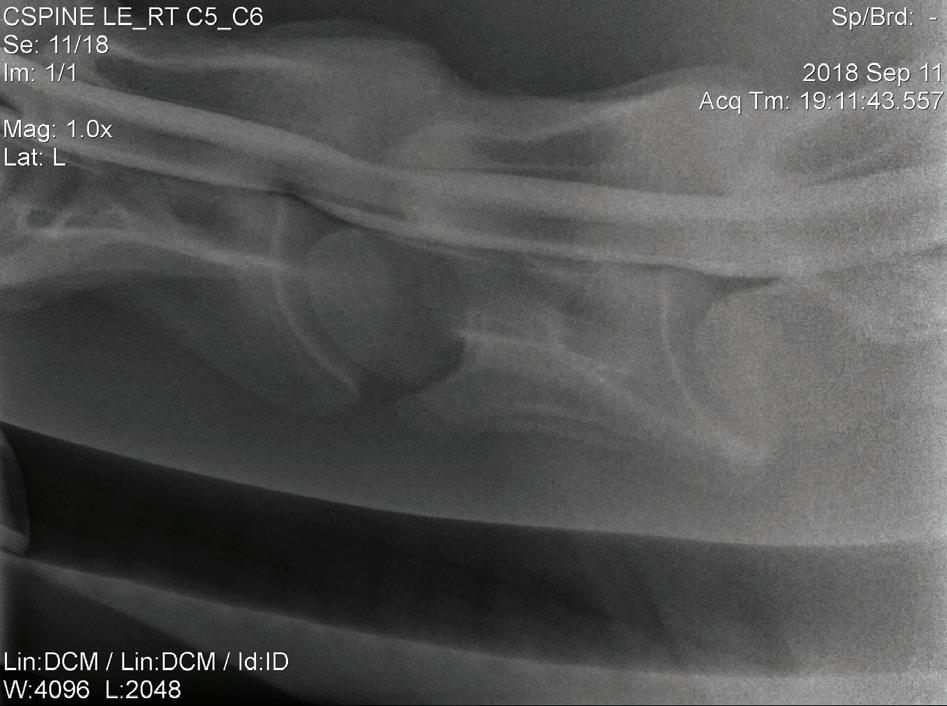

Sex: Gelding

Weight: 563 kg

PRESENTATION

The horse was presented to our hospital on 24 January 2020. The owner reported that the horse was normal before going to the breakers for 5 weeks to begin its education. When arriving home, the horse was immediately noted to have a hind limb problem (when circling), with a swollen left hind leg. Since this time, intermittent abnormalities were suspected by the owner. The owner noted that the horse had lost weight since being at the breakers.

INITIAL DIAGNOSTICS

Neurological examination

A neurological examination can be divided into four sections2:

1. Evaluation of mental status (observing the horse from a distance e.g. in a stable or yard)